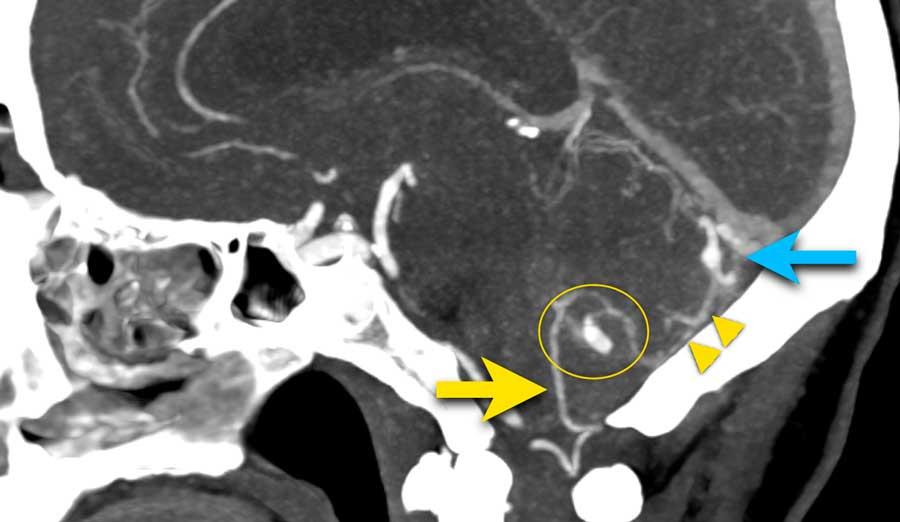

Tiếp tục với DSA…

DSA xác nhận PICA phải kèm túi phình (mũi tên) dẫn đến nidus (vòng tròn).

Nidus được dẫn lưu bởi cả tĩnh mạch nông và tĩnh mạch sâu (không hiển thị riêng biệt ở đây).

Các phát hiện phù hợp với AVM – Spetzler-Martin độ 2:

- Nidus nhỏ (<3 cm): 1 điểm

- Vị trí vùng não không chức năng quan trọng: 0 điểm

- Kiểu dẫn lưu tĩnh mạch bao gồm cả thành phần nông và sâu: 1 điểm

Túi phình hình túi xuất phát từ PICA được giải thích là túi phình liên quan đến dòng chảy.

Do sự thay đổi huyết động học gây ra bởi AVM, thành mạch có thể bị suy yếu và hình thành túi phình.

Các hình ảnh cho thấy DSA trước và sau khi đặt coil túi phình.

PICA, nidus và các tĩnh mạch dẫn lưu bất thường (cùng tạo thành AVM) vẫn còn ngấm thuốc tương phản.

Quyết định không điều trị trực tiếp AVM mà lựa chọn theo dõi và có thể can thiệp phẫu thuật trong tương lai.